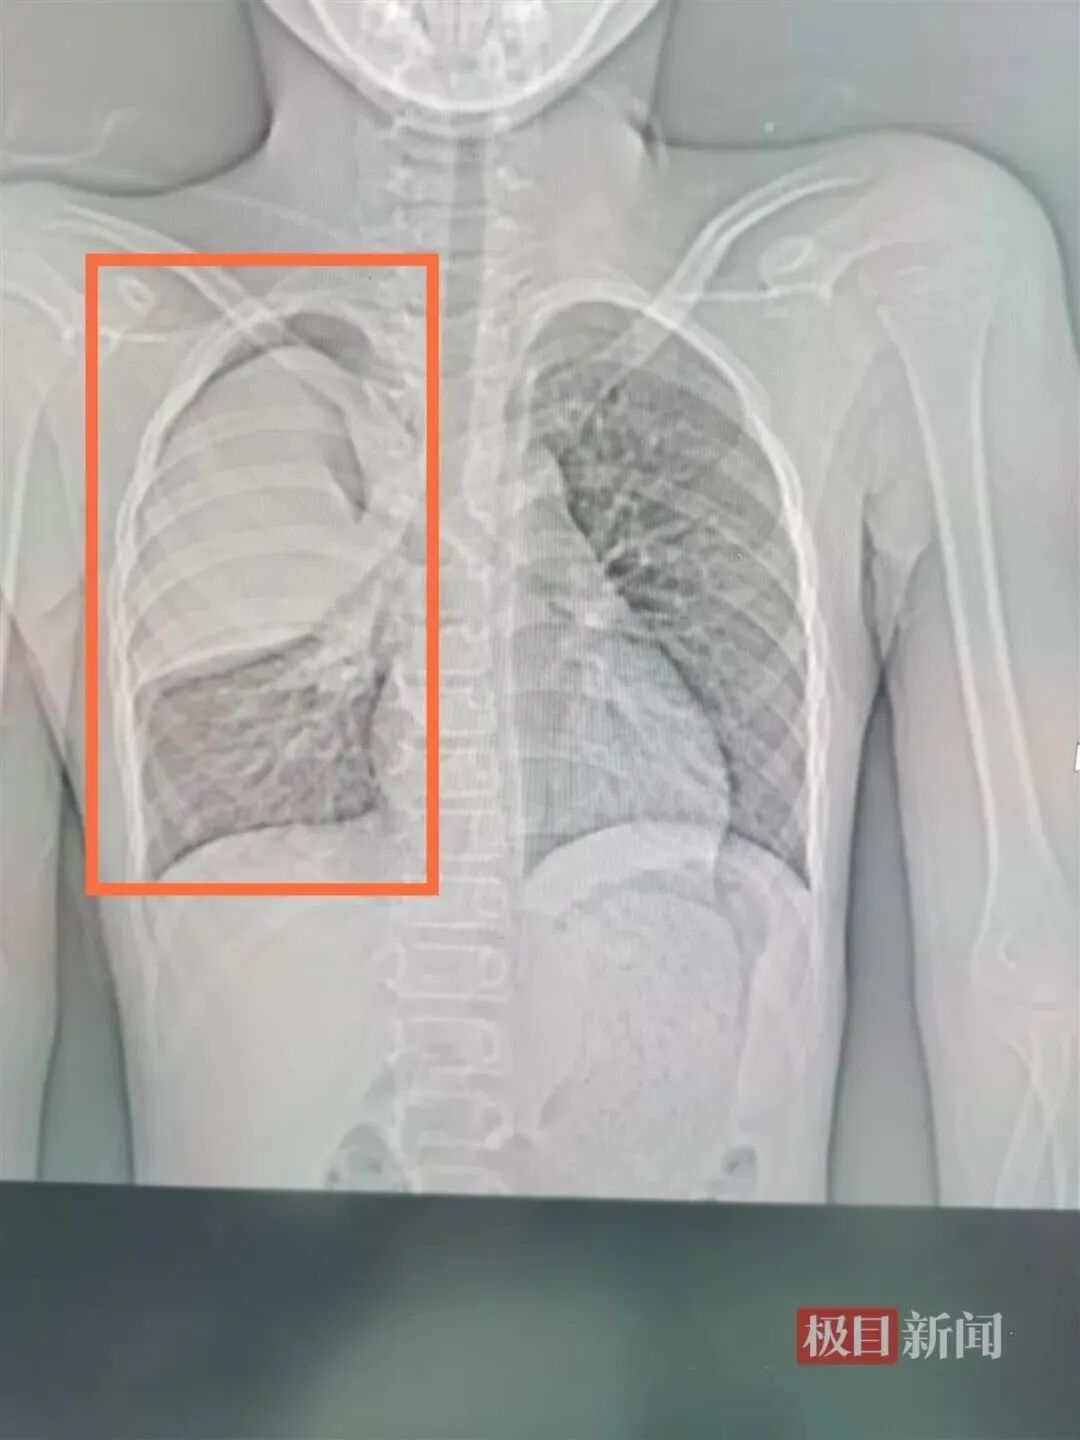

△右上肺三分之二出现白肺。

武汉市肺科医院呼吸二病区副主任杨澄清说,CT检查发现,孩子的右肺“大片状实变”,也就是常说的“白肺”。通过相关检查,小阳的支原体抗体呈阳性,肺炎支原体核酸阳性,随即确诊为肺炎支原体肺炎。

这是因为,肺炎支原体会在人体内激发出人体的免疫反应。从患者胸片,可以看到范围大小不等“白肺”的地方。

杨澄清表示,支原体感染常引起呼吸道感染,常为咽炎、支气管炎,表现为感冒一样,部分具有自限性,部分出现顽固性的干咳,严重者可发展为肺炎甚至重症肺炎,类似小阳这样的患者,就会发展成局部“白肺”,甚至更严重的情况。